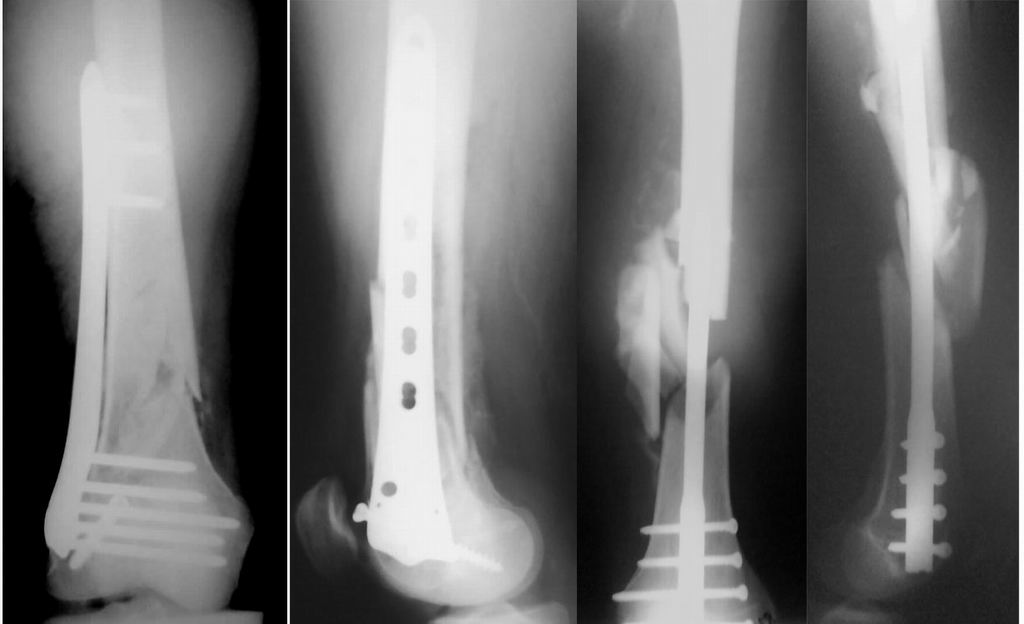

Уважаемые коллеги! От имени Алексея Смирнова всем спасибо за обсуждение. Больной прооперирован. Снимки в приложении.

Имя     : postoperative.jpg